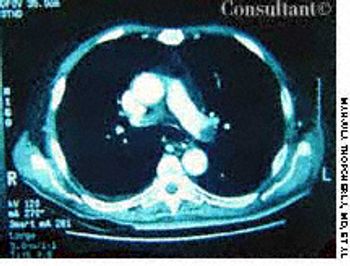

A 2-month history of cough sent a 62-year-old woman for medical evaluation. The patient denied fever, chills, and rigors but reported seeing streaks of blood in her sputum during the past month. The patient had undergone a right nephrectomy 4 years earlier for renal cell carcinoma.